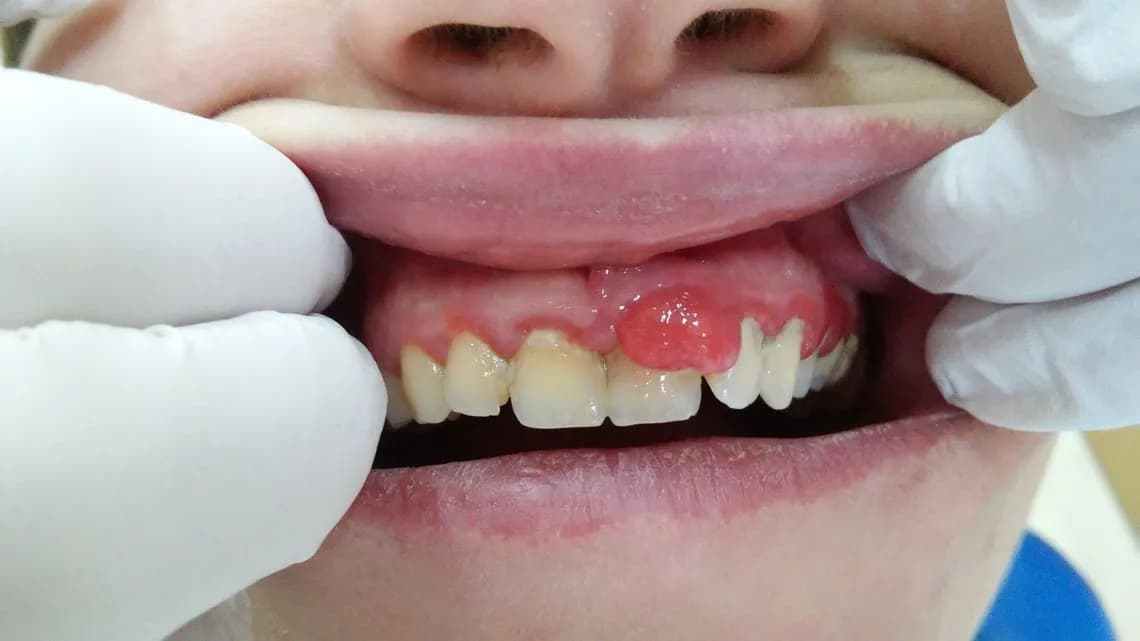

Choroby błony śluzowej jamy ustnej mogą przybierać różne formy i często wymagają interwencji specjalisty. Do najczęstszych schorzeń należą afty, które są bolesnymi owrzodzeniami w jamie ustnej, oraz liszaj płaski, który objawia się swędzącymi, czerwonymi plamami na błonie śluzowej. Oba te schorzenia mogą powodować dyskomfort i utrudniać codzienne czynności, takie jak jedzenie czy mówienie.

Inne poważne zmiany to nowotwory jamy ustnej, które mogą manifestować się jako nietypowe guzki, owrzodzenia lub zmiany koloru błony śluzowej. Ważne jest, aby zwracać uwagę na wszelkie nietypowe objawy, ponieważ wczesne wykrycie takich zmian może znacznie zwiększyć szanse na skuteczne leczenie. Dlatego w przypadku jakichkolwiek wątpliwości, zawsze warto zasięgnąć porady specjalisty.Najczęstsze choroby błony śluzowej jamy ustnej i ich objawy

Wśród chorób błony śluzowej jamy ustnej najczęściej występują afty oraz liszaj płaski. Afty to małe, bolesne owrzodzenia, które pojawiają się na wewnętrznej stronie policzków, języku lub dziąsłach. Objawiają się one jako okrągłe, białe lub żółtawe plamy otoczone czerwonymi brzegami, a ich obecność może powodować znaczny dyskomfort podczas jedzenia czy mówienia. Z kolei liszaj płaski to przewlekła choroba, która objawia się jako swędzące, czerwone plamy z białymi liniami na błonie śluzowej jamy ustnej, często w okolicach policzków i języka.

Inne schorzenia to np. zapalenie błony śluzowej jamy ustnej, które może być spowodowane infekcją, alergią lub podrażnieniem. Objawy obejmują zaczerwienienie, obrzęk i ból w dotkniętych obszarach. Ważne jest, aby zwracać uwagę na te objawy, ponieważ mogą one wskazywać na poważniejsze problemy zdrowotne, które wymagają konsultacji z odpowiednim specjalistą.